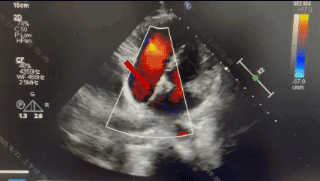

术后1周随访

超声报告:(1)房间隔封堵器位置正常,各瓣叶形态活动未见异常,右心比例稍大,左房室腔不大,心包腔内未见液性暗区; (2)多普勒检查:房水平未见残余分流;心功能:室壁运动协调,未见节段性异常;(3)先天性心脏病房间隔缺损封堵术后未见残余分流。

术后3个月随访